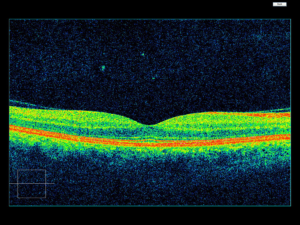

OCT..the diagnostic tool for diseases of retina

Optical coherence tomography (OCT) is a non-invasive imaging test. OCT uses light waves to take cross-section pictures of your retina.

With OCT, your ophthalmologist can see each of the retina’s distinctive layers. This allows your ophthalmologist to map and measure their thickness. These measurements help with diagnosis. They also provide treatment guidance for glaucoma and diseases of the retina. These retinal diseases include age-related macular degeneration (AMD) and diabetic eye disease,vascular occlusions as discussed above.